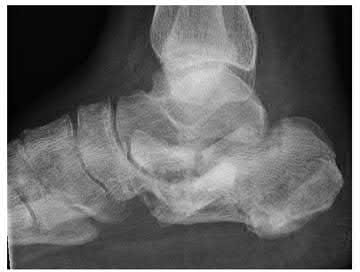

A 70-year-old female with a history of poorly controlled diabetes mellitus presents with purulent ulcers along the plantar aspect of her right forefoot and exposed metatarsal bone. She elects to undergo an amputation. She is insensate to the midfoot bilaterally. Her ankle-brachial index (ABI) for her right posterior tibial artery is 0.4. Further preoperative evaluation demonstrates a transcutaneous oxygen pressure of 45 and an albumin of 3.4. Which of the following would be a contraindication to performing a Syme amputation (ankle disarticulation) in this patient?

A Syme amputation (ankle disarticulation) is a function-preserving amputation option that allows for terminal weight bearing, however strict criteria must be met for a patient to undergo successful Syme amputation. An ankle-brachial index (ABI) less than 0.5 for the posterior tibial artery in a patient with diabetes would be a contraindication for this procedure as success is dependent on the vascular supply of posterior tibial artery to the plantar flap and heel pad.

Pinzur et al retrospectively reviewed their results when performing a single-stage Syme ankle disarticulation in patients with diabetes either for peripheral neuropathy or infection. Patients with ABIs less than 0.5 for the posterior tibial artery had significantly decreased healing rates and smokers had a three-fold increased risk of postoperative infection.